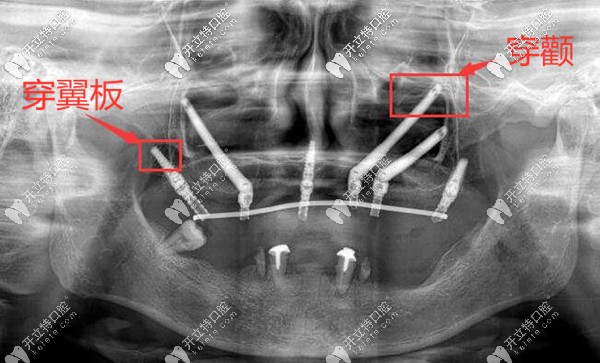

熊院長倡導(dǎo)微創(chuàng)、盡早修復(fù)、長久穩(wěn)定的種植理念。尤其是在上頜骨大量不足的情況下,不用做上頜竇提升、植骨手術(shù);而是采用手術(shù)中少剝離軟組織、不依賴植骨,為顧客做穿顴穿翼板這種可靠的種植手術(shù),并且還能實(shí)現(xiàn)即刻修復(fù)的種植效果。

上頜牙槽骨大量缺失,穿顴穿翼板種植案例▼

深圳正夫口腔熊靖宇穿顴穿翼板種植牙案例